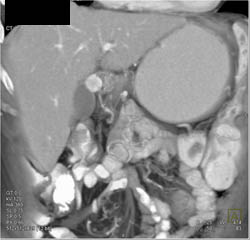

Diagnosis

Multiple Vascular Tumors in Duodenum and Stomachmultiple Vascular Tumors in Duodenum and Stomach